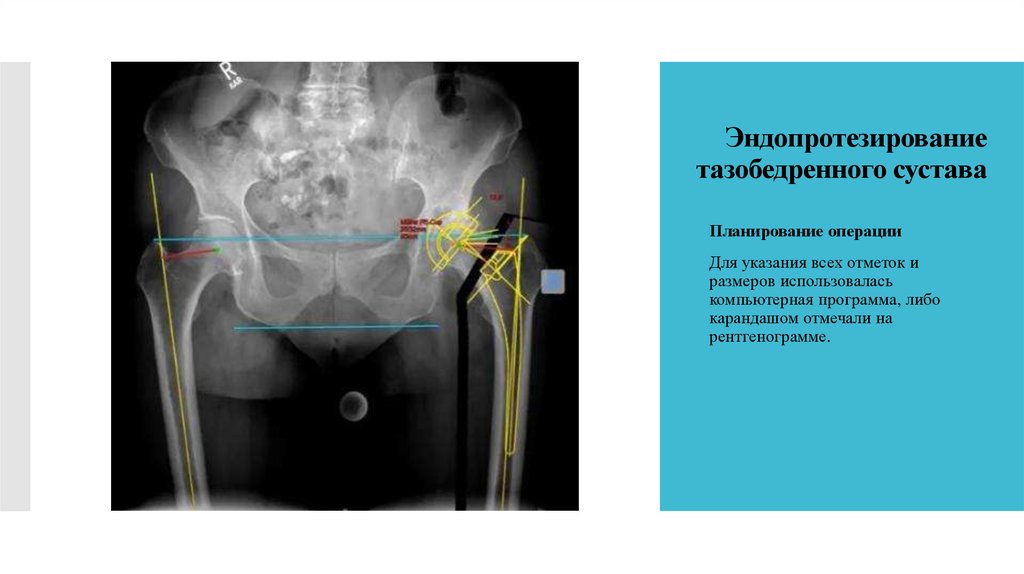

24. Эндопротезирование тазобедренного сустава

Планирование операции

Для указания всех отметок и

размеров использовалась

компьютерная программа, либо

карандашом отмечали на

рентгенограмме.